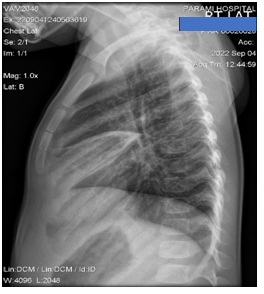

Lateral chest x-ray was also done and it shows